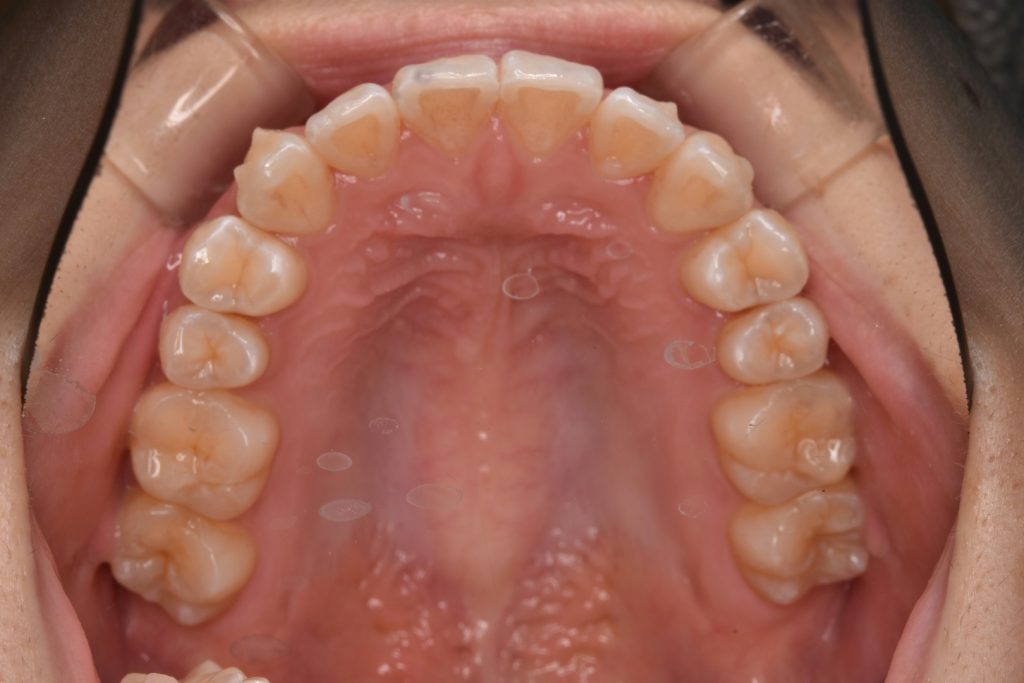

初診時

前歯が空いていて、奥歯でのみ噛んでいる状態です。ガタガタも認められます。